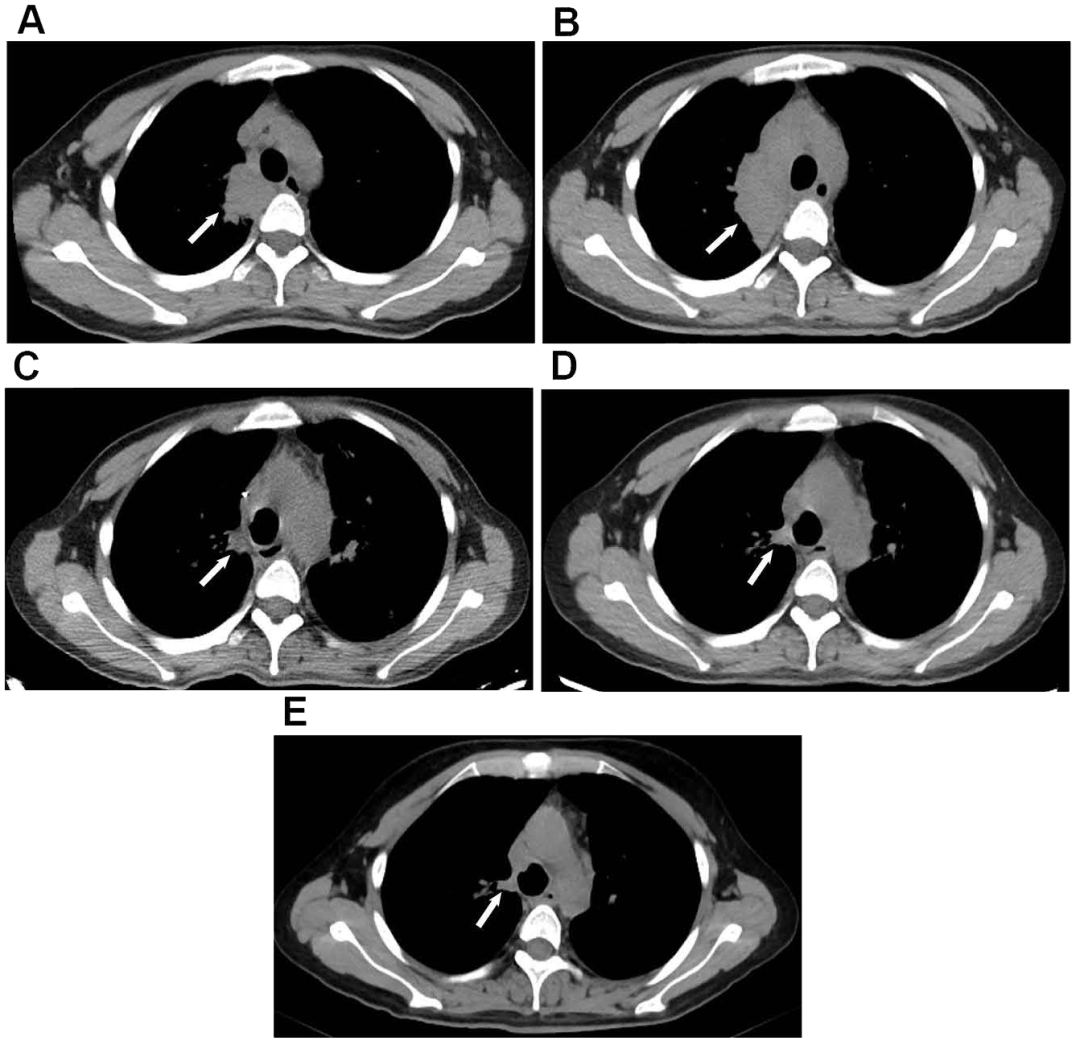

• 胸部电脑断层扫描(CT)显示右上肺斑片状浸润,肺门和纵隔淋巴结肿大(图1A 和B)。

图1:(A和B)显示肺门区淋巴结肿大;(B–E)显示肺门区增大的淋巴结逐渐缩小。

• 2020年5月和8月的胸部CT:肿大的肺门淋巴结已逐渐缩小(图 1B–E),且肺部病变明显吸收(图3A–C)